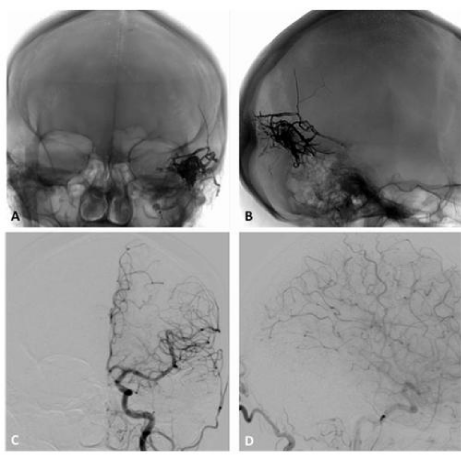

Classification and natural history (Figures 17)

Several classification systems have been developed to describe and guide the treatment of IDAVFs. The most used are Cognard et al.18 and Borden et al.19 classifications. Both are based on the pattern of venous drainage, which reflects the risk of hemorrhage. According to Cognard’s scheme Type I and II IDAVFs drain directly into dural sinus, the difference being the presence in type I of ante grade flow and in type II of retrograde flow into dural sinus (type II a), cortical (pial) veins (type II b) or both (type II a+b) (Figures 14); type III and IV drain directly into cortical (pial) veins, without dural venous drainage, the difference being the presence in type IV of dilated CVD (Figures 57); type V drain into perimedullary veins. Similarly to Cognard’s, Borden’s type I IDAVFs have drainage into a Dural venous sinus or pachimeningeal veins with ante grade flow (Figures 1 & 2) and type III DAVFs have the same dural drainage with retrograde flow into the sinus and/or cortical venous reflux (Figures 3&4), while type III have drainage directly into cortical veins or an isolated segment of dural sinus with cortical venous reflux (Figures 57). According to both systems, the presence of ante grade venous drainage without retrograde flow is associated with a benign clinical course. On the other hand, the factors increasing the risk of aggressive behavior are, in order of importance, the presence of retrograde flow into dural sinus and veins, into cortical or deep veins and the presence of a dilated CVD 7. While Cognard and Borden type I IDAVFs have a benign course with virtually no risk of aggressive symptoms, type II with retrograde flow only into Dural sinuses and pachimeningealveins are associated in about 37% of cases with aggressive symptoms other than hemorrhage. Cognard’s and Borden type II IDAVFs with reflux into cortical veins have a more aggressive course, presenting with intracranial hemorrhage in 10.718 to 18% of cases,19 with an annual hemorrhage rate of nearly 6%, while other aggressive symptoms are present in almost 43% of cases.18 Both classifications find that the risk of hemorrhage greatly increases in case of direct drainage into cortical veins, although Borden’s classification does not make difference between dilated and non dilated CVD, which is the distinctive feature of Cognard’s type IV IDAVFs compared to type III. Several authors report higher bleeding risk in case of venous ectasia (i.e. CVD >5mm and 3 times larger than the diameter of draining vein), regardless of the classification scheme used. Actually, Borden’s type III without dilated CVD, matching Cognard’s type III IDAVFs, present with hemorrhage in 3420 to 40% of cases,18 with an annual hemorrhage rate of 10%, while 76% of Borden’s type III with dilated CVD, corresponding to Cognard’s type IV IDAVFs, show a hemorrhagic presentation and have a 21% annual bleeding rate. Annual hemorrhage risk further increases in case of previous hemorrhage, up to 46%.20 Aggressive symptoms other than hemorrhage have a similar frequency in IDAVFs with reflux into cortical veins regardless the presence of direct CVD, between 36 and 43% of cases. Cognard types V IDAVFs with drainage into perimedullary veins are associated in 50% of cases with myelopathy.18 Borden-Cognard type I IDAVFs may rarely modify and develop CVD, in 1.4% of cases and occasionally display a pial recruitment when enlarging or becoming more diffuse or following partial embolization.20

Figure 2 A. Post-embolization radiography, lateral view, showing the cast of Onyx occluding the middle meningeal artery and the occipital artery through an arterioarterial reflux. B. DSA of the common carotid artery, lateral view, showing complete occlusion of the fistula. C and D, DSA of the common carotid artery, lateral and anteroposterior view, showing the patency of the lateral sinus. The patient had resolution of his pulsatile tinnitus, persisting at a 3 years follow-up. s

Figure 3 A 43-year-old woman developed a left pulsatile tinnitus. A and B (left ECA injection, lateral projection) C and D (left ECA injection, AP projection) DSA showing a Borden and Cognard grade II IDAVF with multiple shunts between the occipital artery (white arrow), parietal branches of the middle meningeal artery (white arrowheads) and left transverse sinus (asterisk). There is retrograde flow into cortical veins (black arrows). Note the associated sigmoid sinus stenosis (black arrowhead), Just upstream to jugular bulb.

Figure 4 A (anteroposterior) and B (lateral), radiography showing the cast of Onyx obliterating the parietal branches of the middle meningeal artery with arterioarterial reflux into homolateral feeders, the cast extending to the arteriovenous junction and the proximal venous outflow. C Anteroposterior and D lateral projections DSA of the common carotid artery demonstrating a complete obliteration of the fistula.